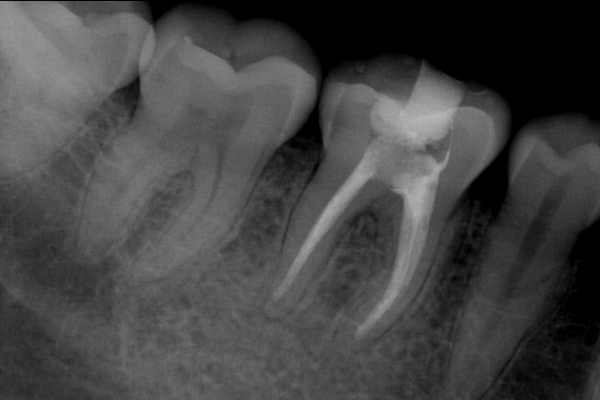

Endo paciente 4

Paciente X de 32 años de edad, llega con fuerte dolor e infección dental

El paciente en su consulta de diagnóstico

Endodoncia terminada

Buen pronóstico a la conservación de la pieza dental